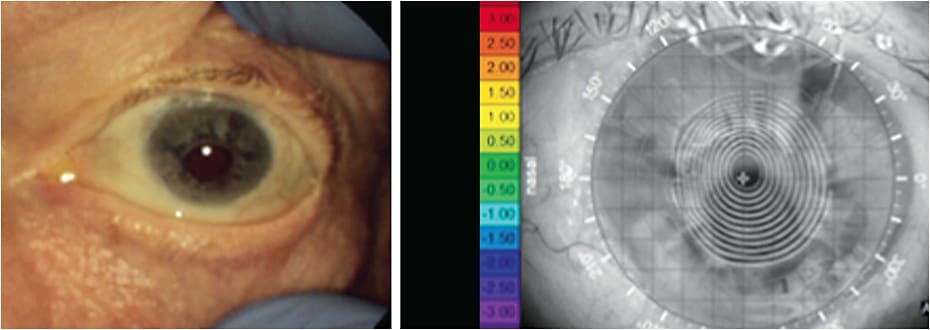

Consider the patient who experienced an alkaline burn to the cornea, the patient who had a thorn enter her left eye; the patient whose weed whacker belt injury penetrated his cornea; the patient who was hit in the eye by a Nerf ball, resulting in a commotio retinae; and the patient whose paint ball injury left her aphakic, with a retinal detachment and aniridia. In all these cases (see subsequent images), the simple use of protective eyewear could have prevented the devastating injuries incurred by these individuals.